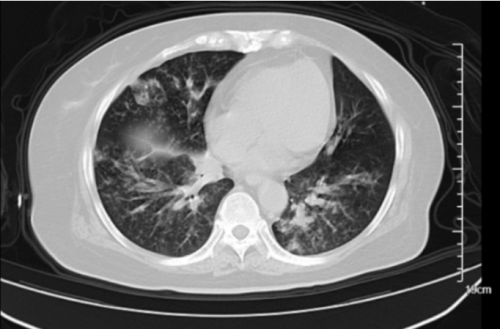

胸部影像学

2025.11.27-11.29

改为经鼻高流量

经过11月21日到11月29日8天抗感染、抗炎、俯卧位通气治疗患者病情好转,吸氧浓度下调,氧合指数得到改善